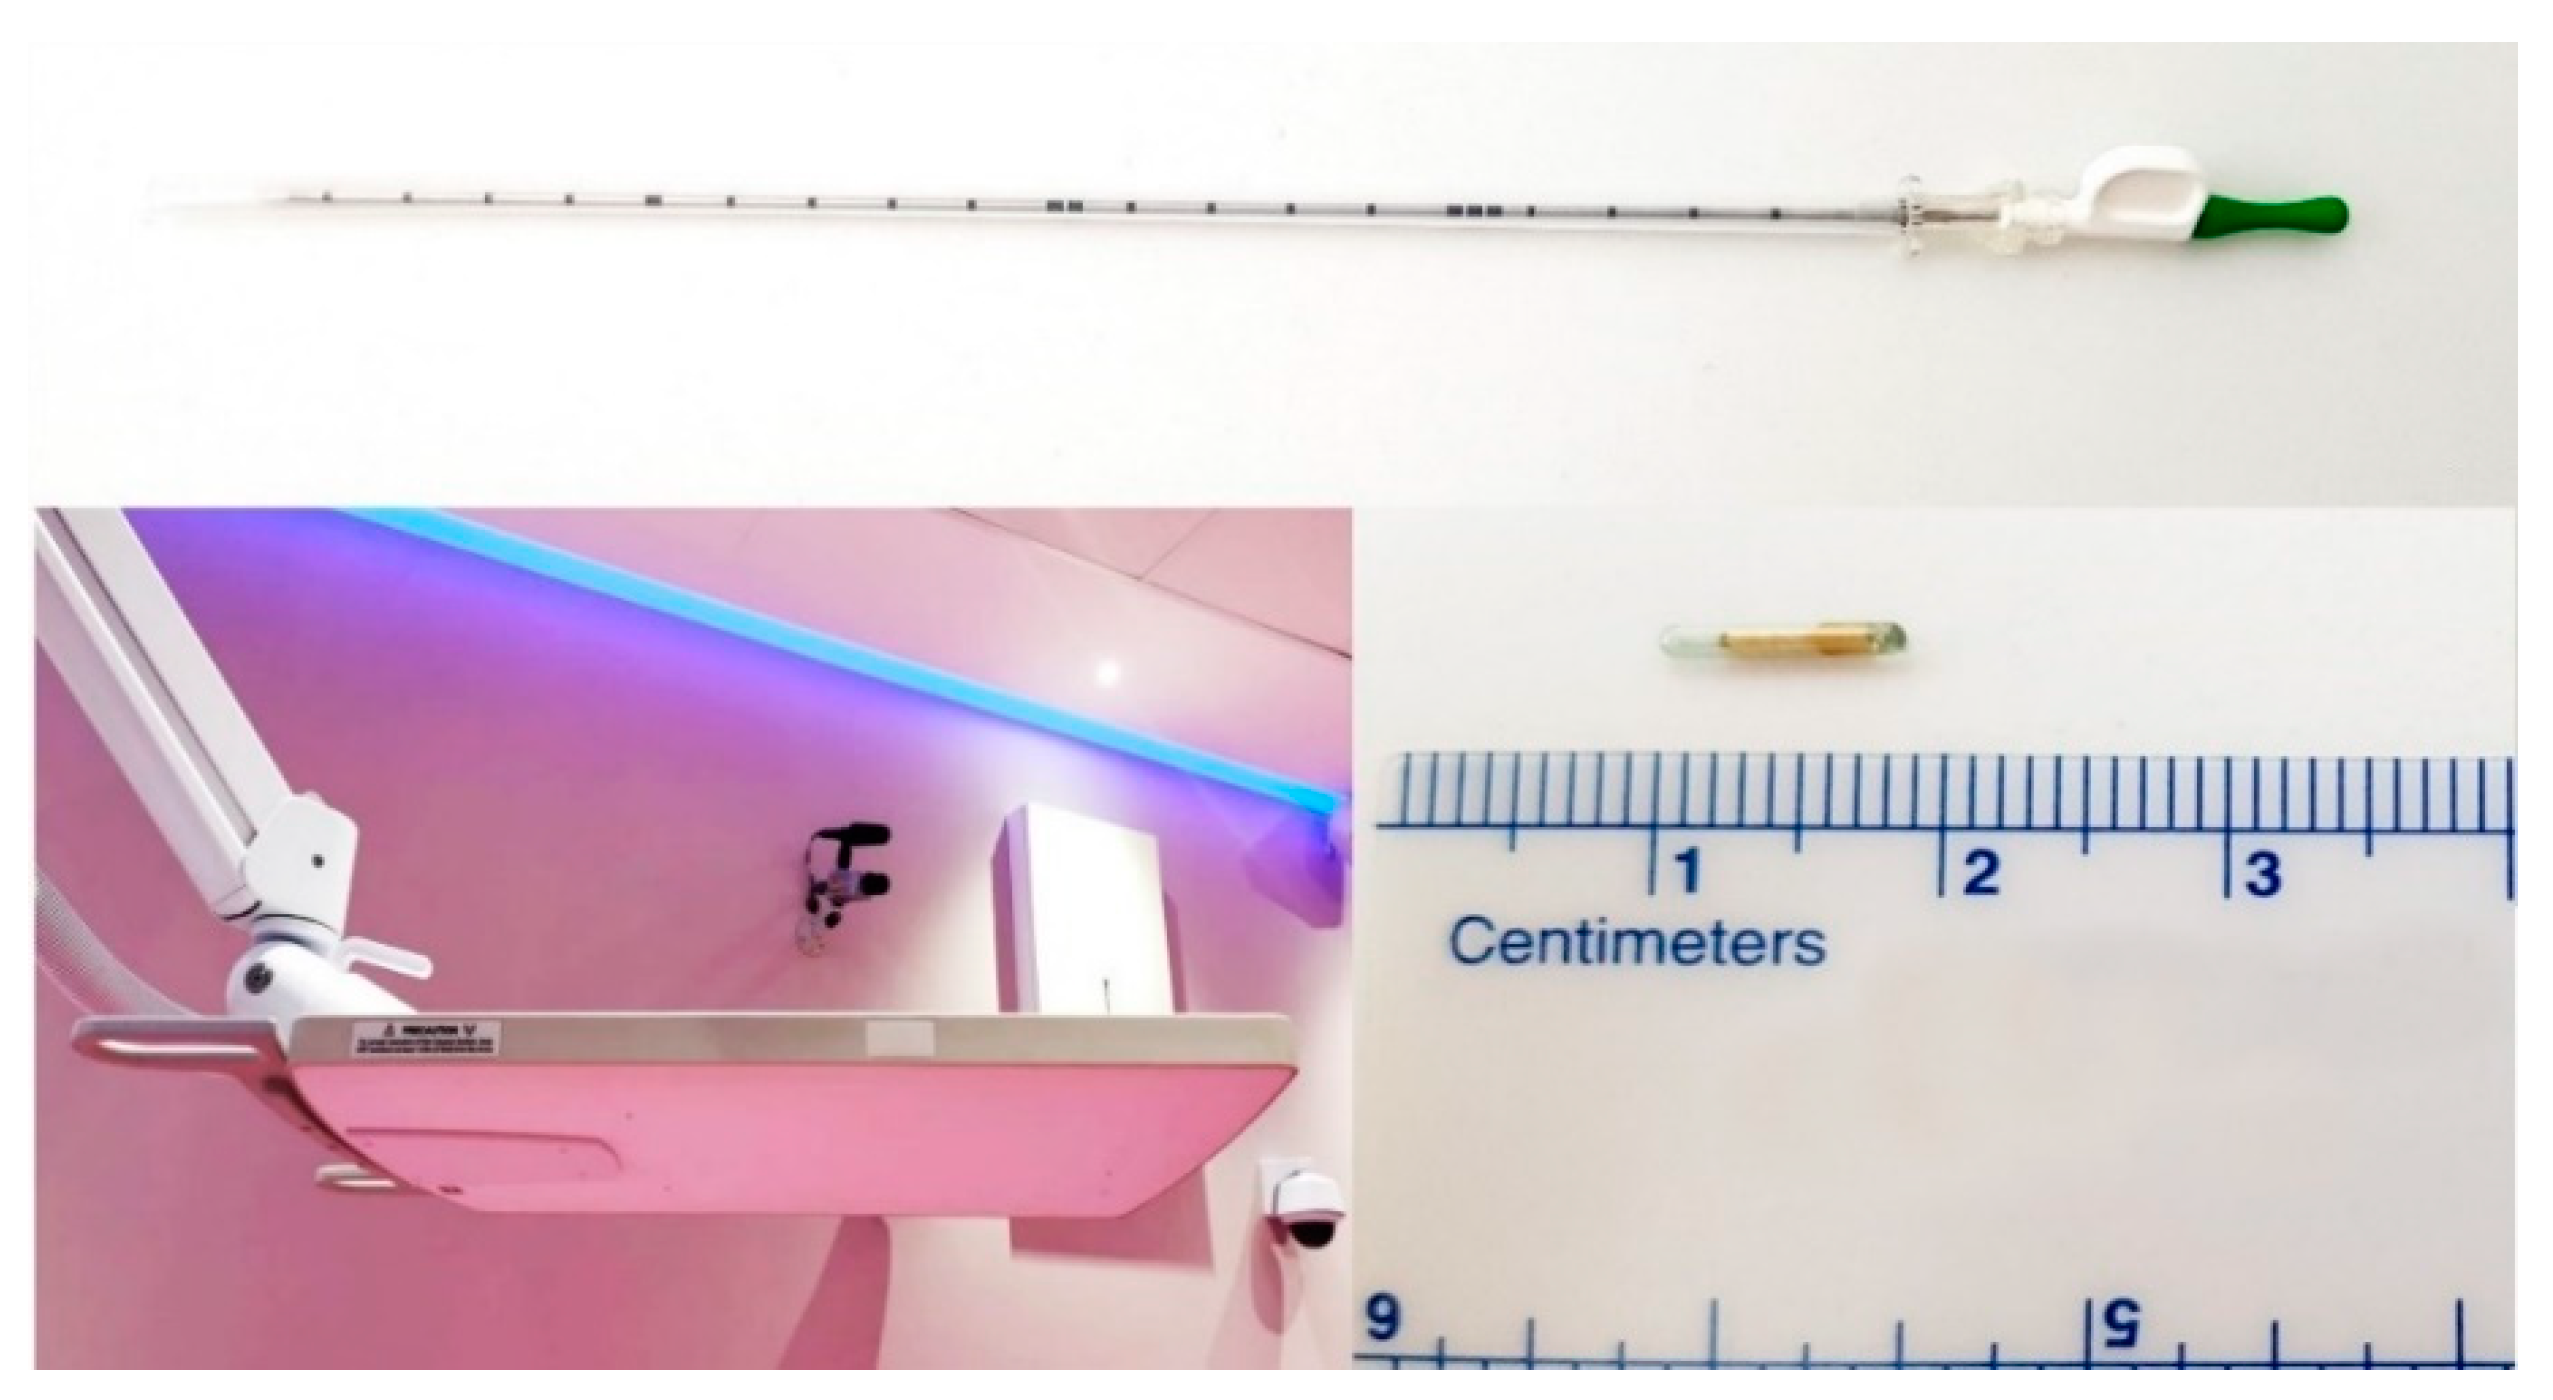

Calypso

® extracranial tracking (Varian Medical Systems, Palo Alto, CA, USA) is a real time intrafractional motion management system, FDA approved for motion management of soft tissue tumor lesions [

23,

24]. The Calypso

® extracranial tracking system consists of Calypso Beacon

® transponders: radio frequency electromagnetic fiducials consisting of a glass envelope which a contains metal coil, and an electromagnetic array (

Figure 1). The electromagnetic array detects the position and movements of each of the transponders implanted into the tumor in three axes (longitudinal, horizontal and sagittal) and in three plains (transversal, coronal and sagittal). The system provides the three-dimensional intrafractional motion management of all movements of the lesion in real time with 20 Hz frequency and submillimeter accuracy. The transponders are hypoallergenic and non-toxic. The Calypso

® system uses non-ionizing radio frequencies to localize the transponder. At least two Beacon

® transponders are needed for the Calypso

® system to detect linear movements, and three transponders are needed to detect rotational movements. Beacon

® transponders were percutaneously implanted into or adjacent to the lesion by an educated and skilled interventional radiologist in our institution under CT-guidance in local anesthesia, using the implantation needle provided by the manufacturer (

Figure 1).

The distance between transponders in the lesion was minimum 1 cm, and maximum 7 cm, according to the manufacturer’s manual, to provide accurate motion tracking (

Figure 2).